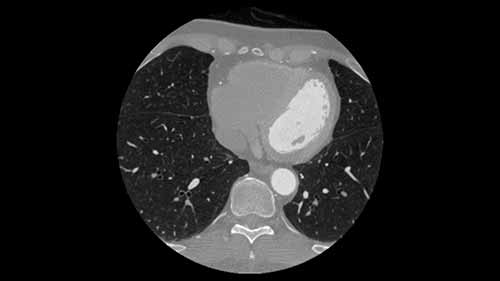

心脏磁共振适成像